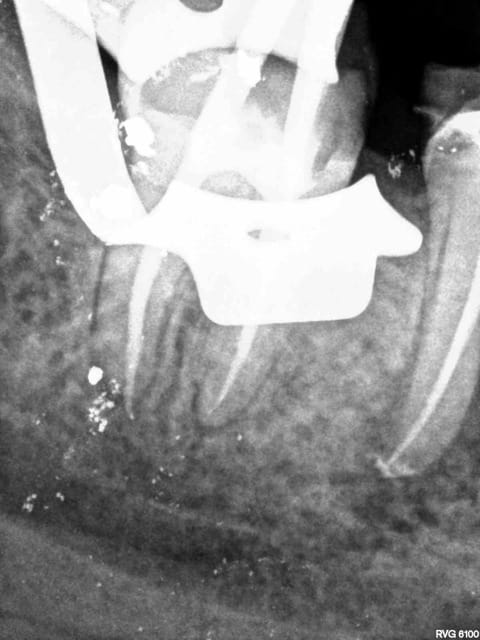

J'y travaille pour trouver un moyen simple et efficace pour poser la digue dans toutes les situations comme celle ci dessous. Tiens c'est tout frais, endo sc33 en 1 temps, 1H 15 et encore je n'ai pas d'assistante au fauteuil.

Technique "Monocône"....C'est un peu "has been" je trouve.... ;-)

Surtout mono-cone sans ciment. mais c'est vrai que quand on ne fait pas d'essayage de cones on ne risque pas de voir pas la différence.-))))

Mais je ne me cache pas que je les scelle de temps en temps. Mais manque de bol pas là. Thermo compactés au mac spaden. Tu vois peut être la différence non ?